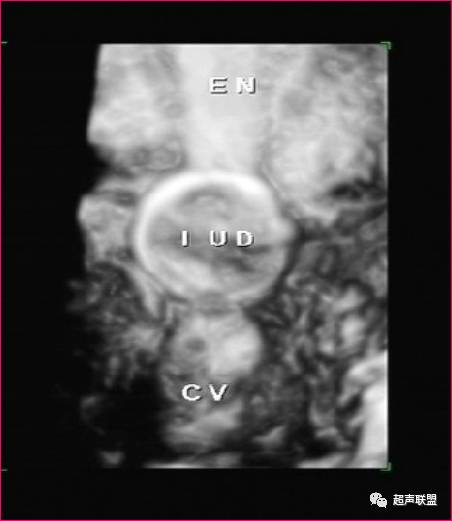

(二)金塑铜IUD

金塑铜IUD基本声像图与不锈钢圆环相似,另可显示短柱回声。

1、纵断面常见二点或三点强回声,中间一点为节育器中间的短柱。 2、横断面常在圆形光环中间见到短柱状强回声。

(四)带铜TIUD

1、纵断面

IUD的纵臂缠绕铜丝,声像图显示直线状较强回声。如在纵臂上镶有45个铜套,则显示45个串珠状或链条状强回声短条,伴有光晕和后方成片声影。强回声长2835mm

2、横断面

前位子宫可显示“T”形强回声,各铜套形成的光晕较强,呈横行条状,排列呈“鱼刺样”强回声。后位子宫可显示“⊥”形强回声。水平位子宫,当探头从宫颈向宫底连续扫查时,显示IUD纵臂呈点状强回声连续出现,至IUD横臂处,呈“—”字形较强回声。